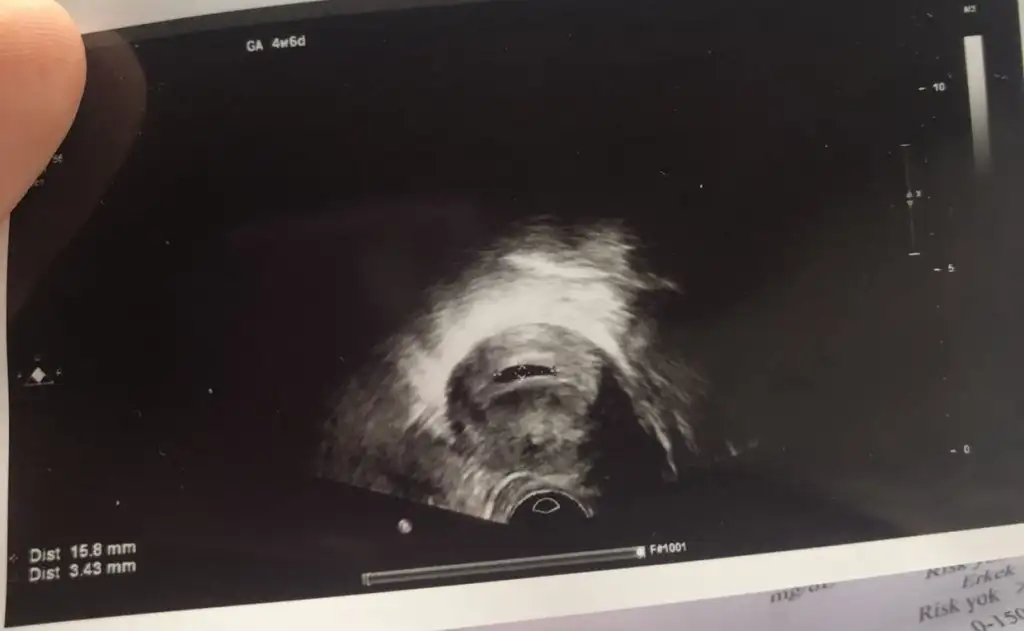

Canım negatif yazan olması gereken ama benim sonucum +1 biraz yüksek inşallah düzelir. Doktor sıkıntı yok deyince rahatladım biraz ama merak ettim her gebelikte olur mu diye. O kadar mutluydum ki keseyi görmeye gideceğimiz gün aşırı heyecan yaptım üstten baktı göremedi daha da stres oldum alttan bakınca gördü çok şükür keseyi.Normalse iyi bari canim +1 yazıyor ama yanında da negatif yazıyor baksana seninkinde

Sorma canım hem çok uğraştık hemde ilk insan biraz garip oluyor tabi. Sürekli bisey olacak mı korkusu. Bende 5+4te alttan bakıp gordu canım sıkıntı yapma zaten benim rahmim tersti karından hemen gözükmeyecek sanırım.Canım negatif yazan olması gereken ama benim sonucum +1 biraz yüksek inşallah düzelir. Doktor sıkıntı yok deyince rahatladım biraz ama merak ettim her gebelikte olur mu diye. O kadar mutluydum ki keseyi görmeye gideceğimiz gün aşırı heyecan yaptım üstten baktı göremedi daha da stres oldum alttan bakınca gördü çok şükür keseyi.

Ee 4+6 daha erkenmiş canım normal gözükmemesiBen sanırım doğurana kadar rahatlayamıcam çok uzun zaman var daha ya sabırsızlanıyorum şimdidenkız ben bi de aşı da yaptırmadım hiç geçen sene geçirmiştim bağışıklık kalmış mıdır sanmam

Benim 4+6 olduğu için gözükmedi sanırım üstten ya da göbüş yağımdan

Ya aslında yolk kesesinden bahsetmedi gözükmedi heralde daha küçük diye onu da taktım kafama. Sadece son adet tarihimi sordu en son yaptığım gün çıkan beta hcgyi. Bende problem mi var dedim hayır önde bile dedi gününe göre Bu sefer de önde diye sıkıntı mı var diye düşündüm gerçekten iyi değilim galiba